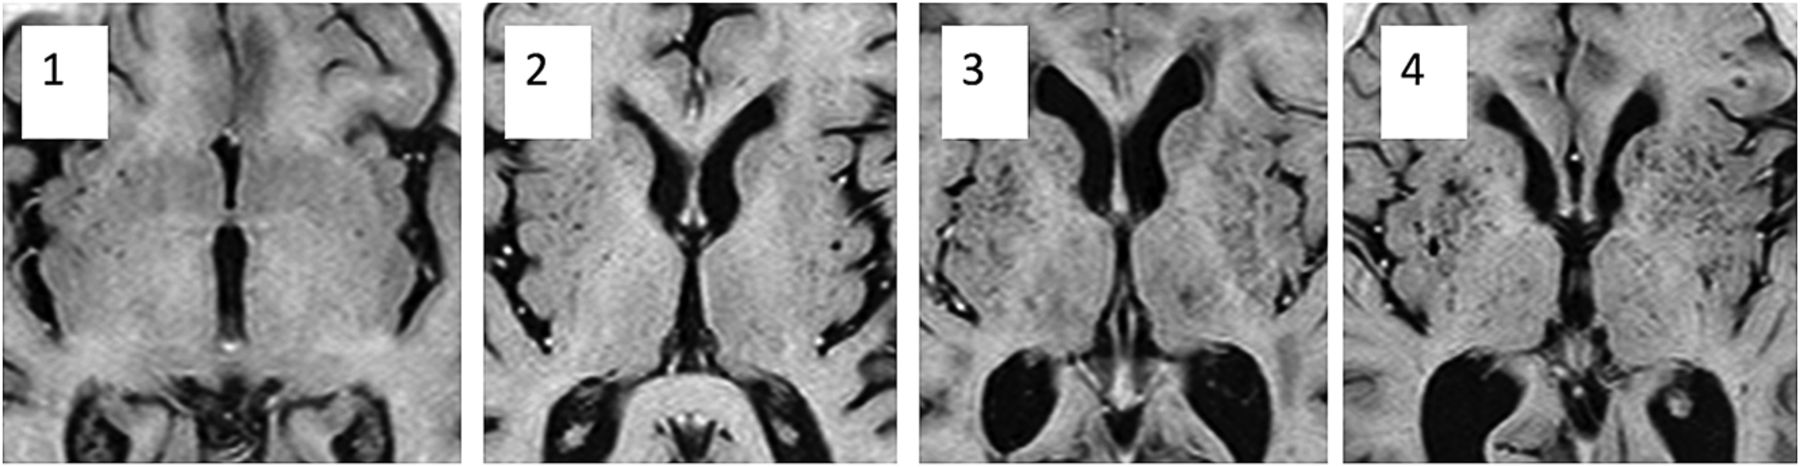

The second scoring system was adapted from Doubal et al, 2010.7 The BG (PVS-2BG) and CSOV (PVS-2CSOV) were scored separately; then, the scores were combined to produce a total score (PVS-2). In each structure, the section with most PVS visible was selected and the number was counted on the side of the brain with the greatest number. Scores were as follows; 0 = no PVS, 1 = 1–10, 2 = 11–20, 3 = 21–30, 4 = 31–40, and so on. The original Doubal score had 3 = 21–40, and 4 (>40 PVS) was the maximum score (Fig 1).

Images show dilated perivascular spaces in the basal ganglia corresponding to PVS-2BG scores of 1–4.